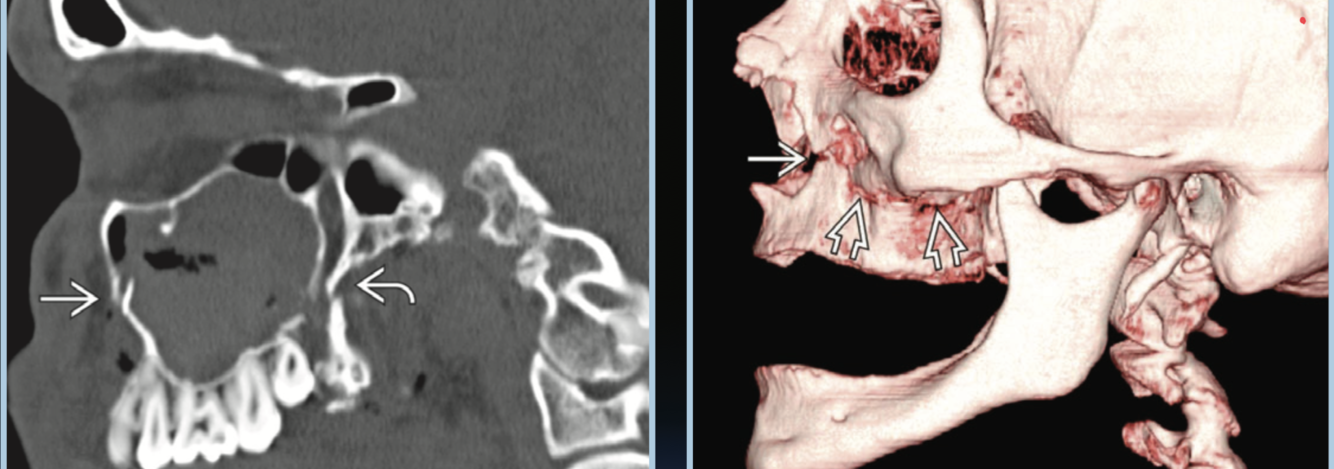

LeFort types?